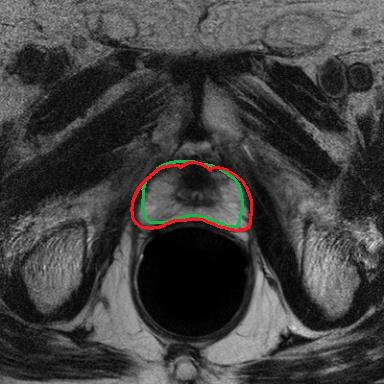

Modern deep neural networks struggle to transfer knowledge and generalize across diverse domains when deployed to real-world applications. Currently, domain generalization (DG) is introduced to learn a universal representation from multiple domains to improve the network generalization ability on unseen domains. However, previous DG methods only focus on the data-level consistency scheme without considering the synergistic regularization among different consistency schemes. In this paper, we present a novel Hierarchical Consistency framework for Domain Generalization (HCDG) by integrating Extrinsic Consistency and Intrinsic Consistency synergistically. Particularly, for the Extrinsic Consistency, we leverage the knowledge across multiple source domains to enforce data-level consistency. To better enhance such consistency, we design a novel Amplitude Gaussian-mixing strategy into Fourier-based data augmentation called DomainUp. For the Intrinsic Consistency, we perform task-level consistency for the same instance under the dual-task scenario. We evaluate the proposed HCDG framework on two medical image segmentation tasks, i.e., optic cup/disc segmentation on fundus images and prostate MRI segmentation. Extensive experimental results manifest the effectiveness and versatility of our HCDG framework.